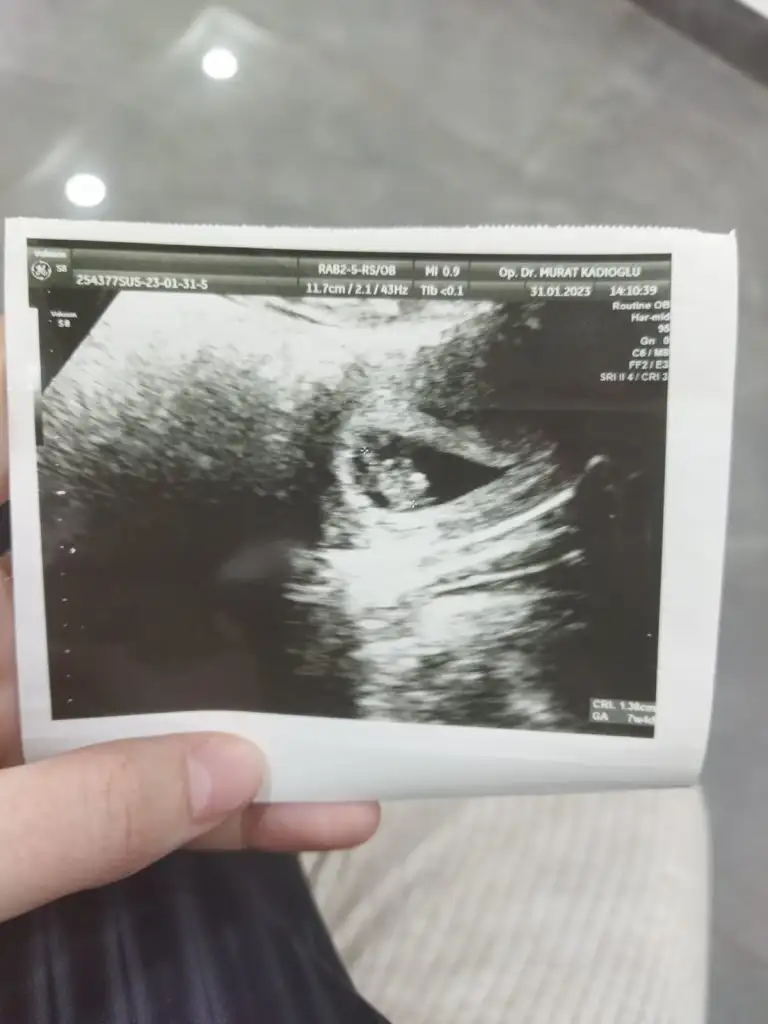

Bak mesela ilk foto oğlumun ilk ulturoson resmiydi ikincisi simdikinin ilk kese fotoğrafiGeçen sefer doktorum dördüncü aya kadar kız demişti ben aldım kıyafetleri felan pembiş pembiş bir ay sonra kontrole bi gittim dedi kız değil erkekşaşkınlıktan inanmamıştım hep kız istiyordum çünkü bide başta kız deyince dönmez artık demiştim ama oluyormuş bazen saklıyormuş bakalım bu sefer de gönlüm kızdan yana ama nasip

Durduğu yere göre mi belli oluyor cinsiyeti ben hiç anlamıyorum daBak mesela ilk foto oğlumun ilk ulturoson resmiydi ikincisi simdikinin ilk kese fotoğrafi

O zaman senin kız geliyorBak mesela ilk foto oğlumun ilk ulturoson resmiydi ikincisi simdikinin ilk kese fotoğrafi

Fasulye tuttu oğlum oldu simdikide yuvarlak bakalım kizmi olucakO zaman senin kız geliyorşuan keseler farklı çünkü birbirinden. Bakalım kese teorisi tutacak mı Yuvarlak olunca kız fasulye gibi olunca erkk diyorlar ya